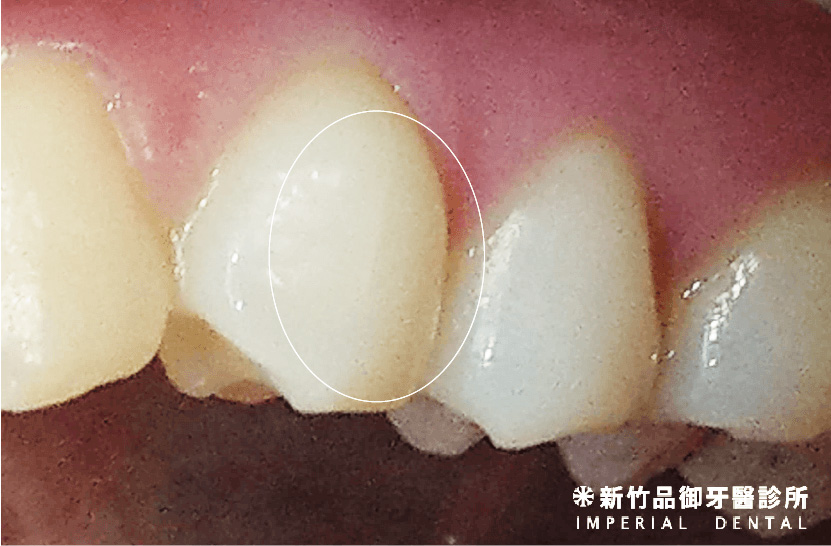

一、裂紋 (Craze lines)

品御牙醫診所 徐孟弘醫師提供

敘述:在琺瑯質上面出現裂痕。

症狀:通常沒有症狀。

處置:一般不做治療,定期回診觀察為主。